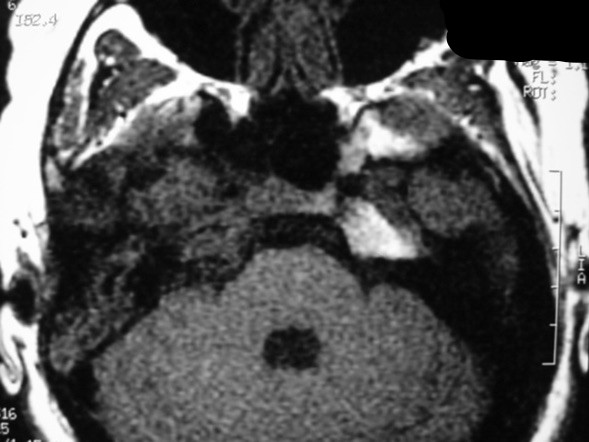

The petrous apex is a relatively inaccessible area that can occasionally harbor serious disease. Disease processes that usually cause symptoms are typically inflammatory or neoplastic in nature. Petrous apex lesions typically cause nonspecific symptoms such as headache, but as the lesion becomes more extensive, adjacent structures such as cranial nerves can become involved. A common early and specific sign of a petrous apex process is abducens palsy. Current imaging techniques can usually provide enough supplemental information to allow a focused plan of treatment. It is important to determine whether a petrous apex lesion can be observed or, if surgical treatment is required, whether a drainage or excision is required. There are various available surgical approaches to the petrous apex. The choice depends on the status of hearing function as well as the suspected pathology, which will dictate whether a drainage or excisional procedure is required.

- Summarize the types of pathology that can occur in the petrous apex, the imaging required, and proper interpretation of information so that a proper differential diagnosis can be formulated.